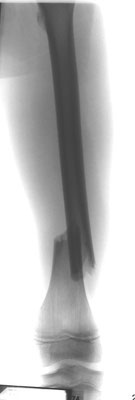

14- jähriger Junge mit Unterschenkelbruch. Minimal-invasive Stabilisierung mit Markdrähten. Das Bein kann bei optimaler Anwendung der Drähte bereits nach einer Woche mit 15 kg an Gehstützen belastet werden.

Stark verschobener Unterschenkelbruch bei einem 14- jährigen. Minimal-invasive Stabilisierung mit winkelstabiler Platte. Das Bein kann nach Abklingen der akuten Schwellung bereits wieder mit 15 kg an Gehstützen belastet werden. Volle Belastbarkeit nach 6 – 10 Wochen.